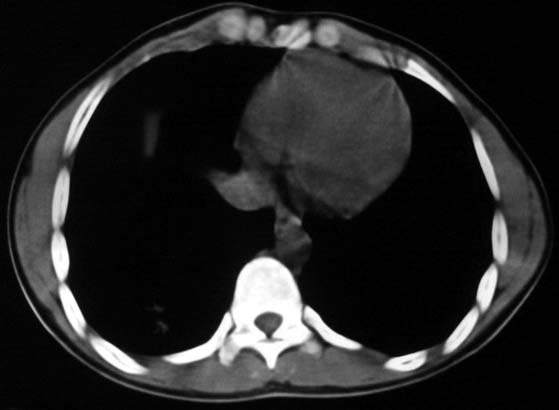

标题: CT5614:外伤病人男,20岁,右上腹痛.余肺野(-) [打印本页]

标题: CT5614:外伤病人男,20岁,右上腹痛.余肺野(-)

最后一幅图像病灶区可分椎旁肋骨骨折可能?请示骨窗,结合外伤史考虑右下肺挫伤。

最后一幅图像示椎旁肋骨走形欠自然,请示骨窗,结合外伤史考虑右下肺挫伤。

支持肋骨骨折,肺挫裂伤。